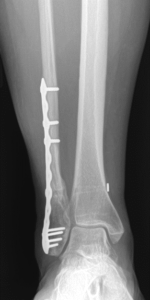

Nonunion and malunion repair related to post-traumatic conditions and/or prior surgery

Acute fracture care of the pelvis and the extremities